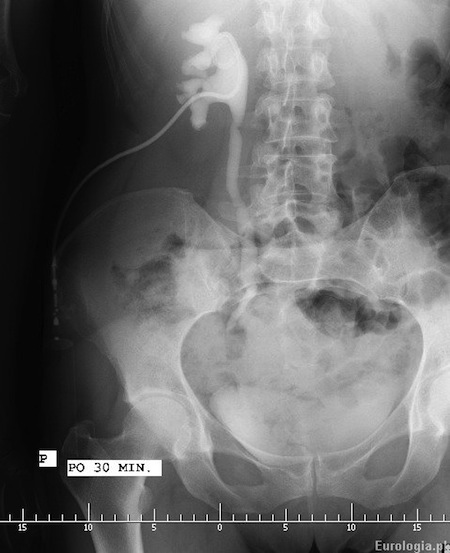

Fot. Pieloureterografia zstępująca wykonana u pacjenta po 30 minutach od podania środka kontrastującego do drenu nefrostomijnego. W opisywanym przypadku dren nefrostomijny założony był kilka tygodni wcześniej z powodu roponercza w przebiegu kamicy prawego moczowdu - złóg tuż poniżej prawego stawu krzyżowo - biodrowego.